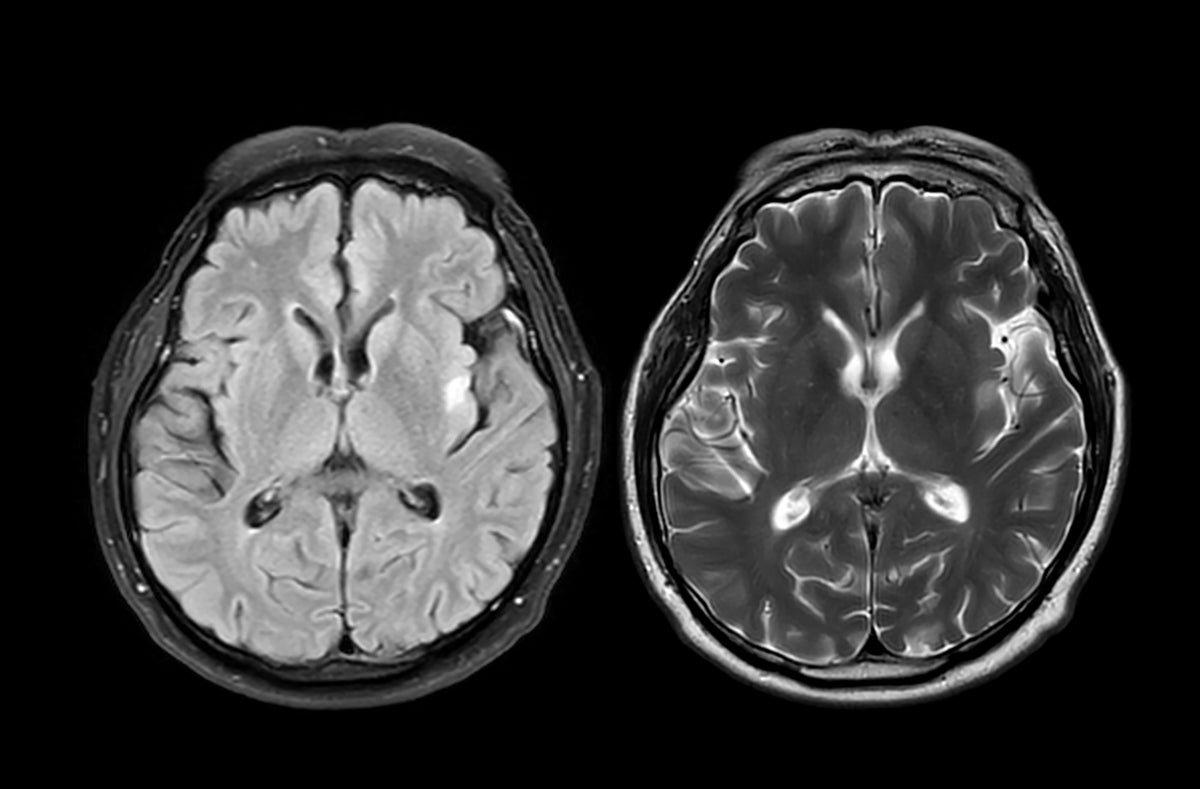

Researchers in the U.K. analyzed brain scans from nearly 1,000 healthy adults before and during the COVID-19 pandemic. What they found was surprising: people living through the pandemic showed signs of accelerated brain aging. Their brains appeared about five and a half months older than expected when compared to prepandemic trends.

So how did they figure this out? The scientists used data from the U.K. Biobank, a massive health database that includes brain imaging from tens of thousands of participants. They trained a machine-learning model to estimate “brain age” based on hundreds of structural features seen in MRI scans. Then they compared two groups: people who had both scans before the pandemic and those who had one scan before and one during the pandemic.